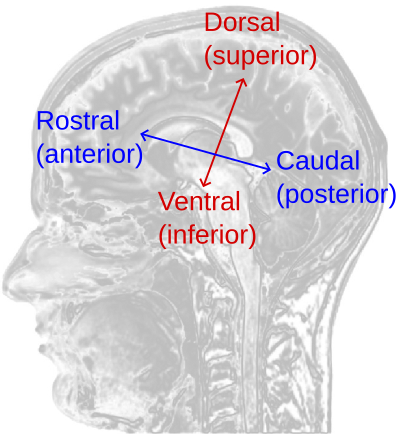

Anatomical planes (useful to imagine as slices):